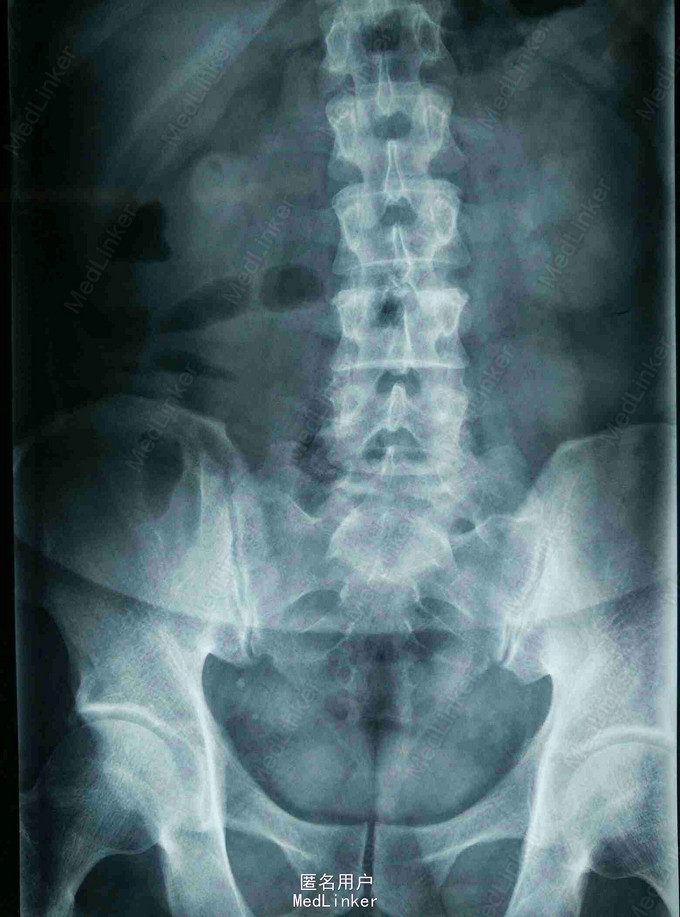

患者,男,45岁,因“腰痛伴右下肢放射痛1月,加重3天”入院。既往身体健康。

查体:脊柱无畸形,腰部L5S1间隙处轻压痛,脊柱无叩击痛,右小腿外侧及足底触痛觉减退,右下肢肌力4级,右下肢直腿抬高试验40度。 MRI提示:L5S1椎间盘脱出,髓核游离要椎管。

诊断:L5/S1椎间盘脱出(右侧) 治疗:因保守治疗效果不佳,准备行手术治疗。